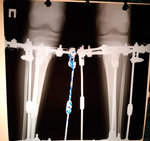

Исходник - 10 лет. Ашхабад.

Дианоз: Варусная деформация обеих оленей. Ротация с обеих сторон 35 градусов. Плоскостопие тяжёлой степени. Начальное явление артроза суставов ниних конечностей.

Дата операции - 16.04.2019г.

IMG_2484-16-04-19-07-27.JPG

IMG_2496-16-04-19-07-27.JPG